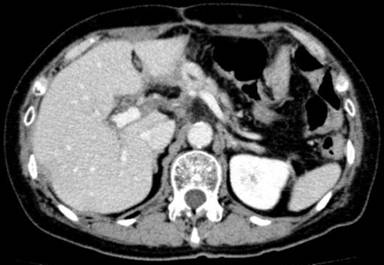

A 62-year-old woman with abdominal pain was found to have a lower biliary carcinoma. A pylorus-preserving pancreaticoduodenectomy (using the Traverso technique) with a lymph node dissection was performed. Pancreaticojejunal anastomosis was performed in an end-to-side fashion. The pancreatic duct and the jejunal mucosa were fixed. The stump of the pancreas and the jejunal wall were approximated with interrupted sutures, which were inserted through the anterior wall of the pancreas through the pancreatic parenchyma to the posterior wall. Sutures were then passed through the seromuscular layer of the jejunum, in the posterior-to-anterior direction, wide enough to cover the cut surface of the pancreas. A catheter with multiple side-holes was inserted into the pancreatic duct and sutured into place as an external stent. The stent tube was guided externally through the stump of the jejunal loop and fixed to the abdominal wall. Histological and immunohistochemical studies resulted in the diagnosis of a biliary carcinoma with lymph node metastases. The postoperative course was uneventful and the patient was discharged from the hospital 16 days postoperatively. The external stent of the pancreatic duct was removed on the 28th postoperative day. After removal, there was no output of fluid from the drain. After discharge, the patient was followed up with computed tomography (CT), ultrasonography (US), and laboratory examinations every 3 months in the outpatient ward. No notable findings were obtained (Figure 1). One year after surgery, she was admitted to our hospital for abdominal pain. All laboratory parameters, including the serum levels of tumor markers, were normal. Abdominal CT and US revealed a fluid collection around the pancreaticojejunal anastomosis (Figure 2). The size of the fluid collection was 45x33x20 mm. US-guided drainage of the fluid collection was performed. A catheter was inserted percutaneously and the fluid collection was drained. Discharge showed a gram-negative rod in the culture, and the amylase value of the discharge was significantly elevated (119,500 IU/L). Contrast radiography of the drainage tube showed no significant collection (Figure 3) and the tube was clamped. The patient was discharged from the hospital without symptoms. We evaluated the pancreatic fistula by CT and US. There was no fluid collection around the pancreaticojejunostomy.

Figure 1. Abdominal CT scan showing no remarkable findings. |